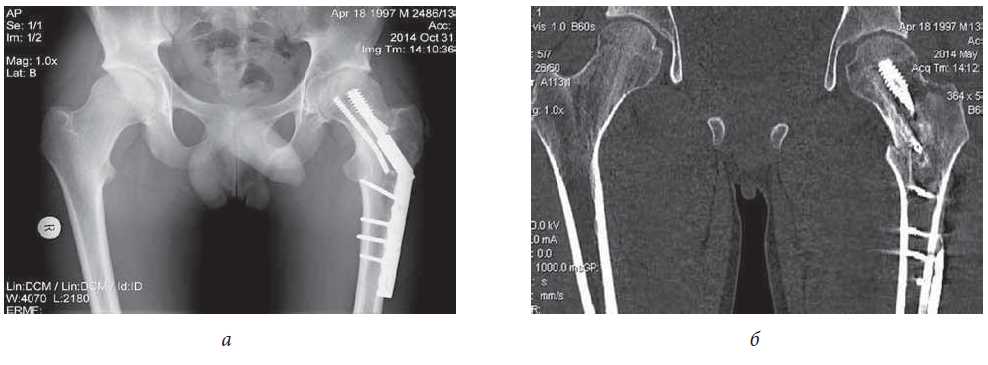

Eleven months after the primary injury, the patient experienced a repeated fracture of the left femur neck with a displacement of the fragments and destabilization of the surgical hardware following a rear impact of the footboard of the moving electric train to the region of the left hip joint (Fig. 6, a, b).

Fig. 6. Patient M., 14 years old: a, b - X-ray and CT of hip joints 11 months after repeated fracture of femoral neck with displacement of fragments and destabilization of metal structures: violation of the integrity of the femoral neck in the basicervical zone with fracture of one cannulated screw and deformation of the other , absence of trophic disorders in the pituitary epiphysis

Surgical treatment was performed for the partial removal of surgical hardware, followed by the closed reposition of the femoral neck fragments with DHS plate fixation (Fig. 7, a, b). Given the patient’s history, an open repositioning with complete removal of the surgical hardware was not an option because of the increased risk of aseptic necrosis of the femoral head that could result from additional trauma to nutrient vessels of the femoral epiphysis in the course of capsulotomy and bone fragments mobilization.

Fig. 7. Patient M., age 14: a, b - radiograph and CT of hip joints after repeated closed repositioning, partial removal of metal structures and osteosynthesis by a dynamic femoral screw (DHS) in a direct projection: restoration of angular values corresponding to the contralateral limb